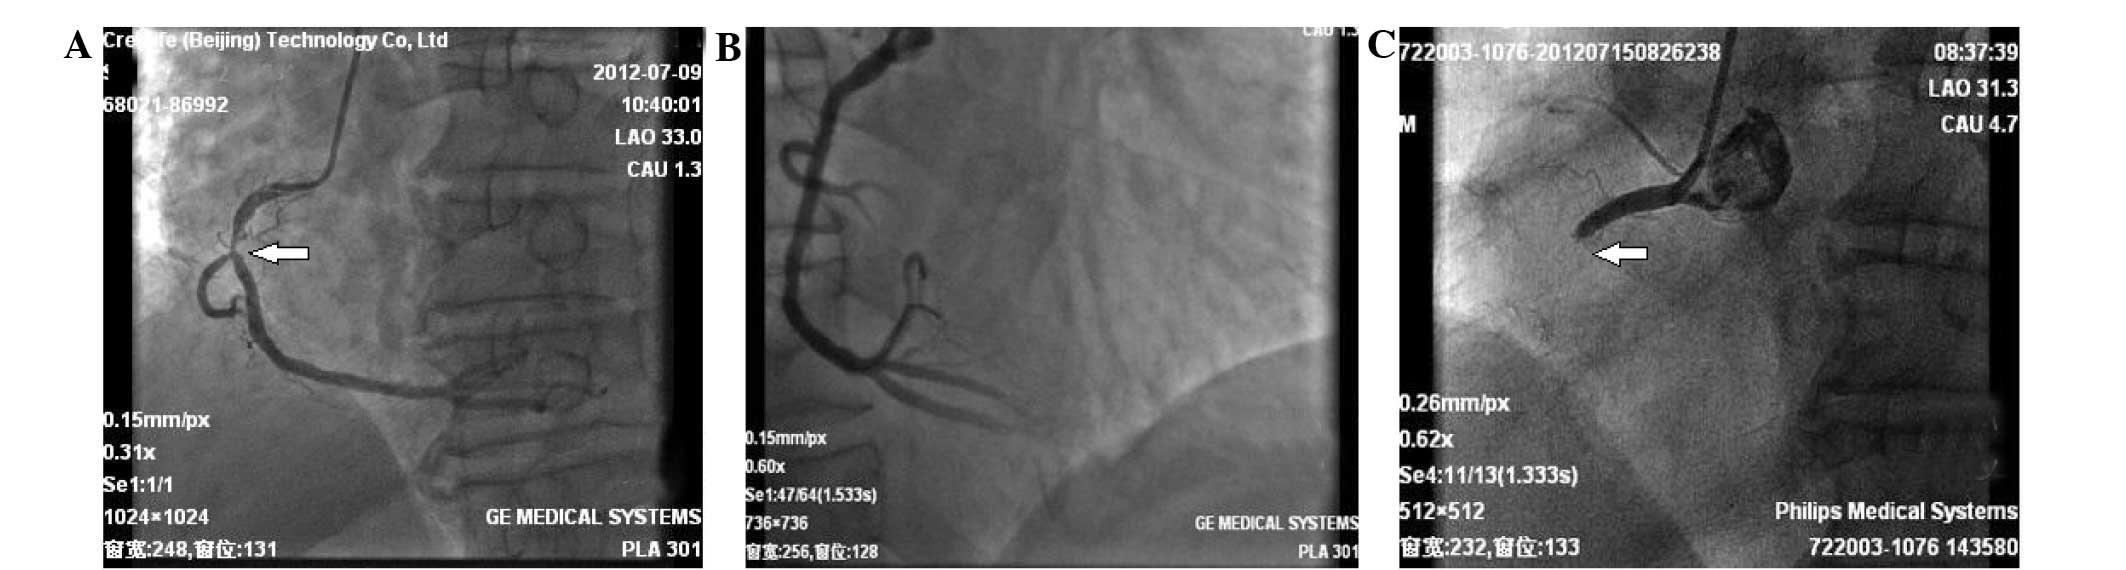

Following intensified antiplatelet treatment with 300 mg clopidogrel and 100 mg aspirin, a repeat coronary angiography (Philips Medical Systems, Eindhoven, Holland) was performed, which showed in-stent thrombosis and total occlusion of the right coronary artery (Fig. 2). After thrombus aspiration, another sirolimus-eluting stent (3.5×33 mm; Firebird; MicroPort Medical Group, Co., Ltd., Shanghai, China) was implanted, and a Thrombolysis In Myocardial Infarction blood flow at level 3 was restored. Dual anti-platelet therapy with 100 mg of aspirin and 150 mg of clopidogrel was applied. Heparin was injected intravenously for anticoagulation.

Figure 2.

Coronary angiography. (A) Approximately 90% stenosis of the right coronary artery (arrow) was observed. (B) A drug-eluting stent was successfully implanted. (C) Right coronary acute stent thrombosis and total occlusion of the right coronary (arrow).